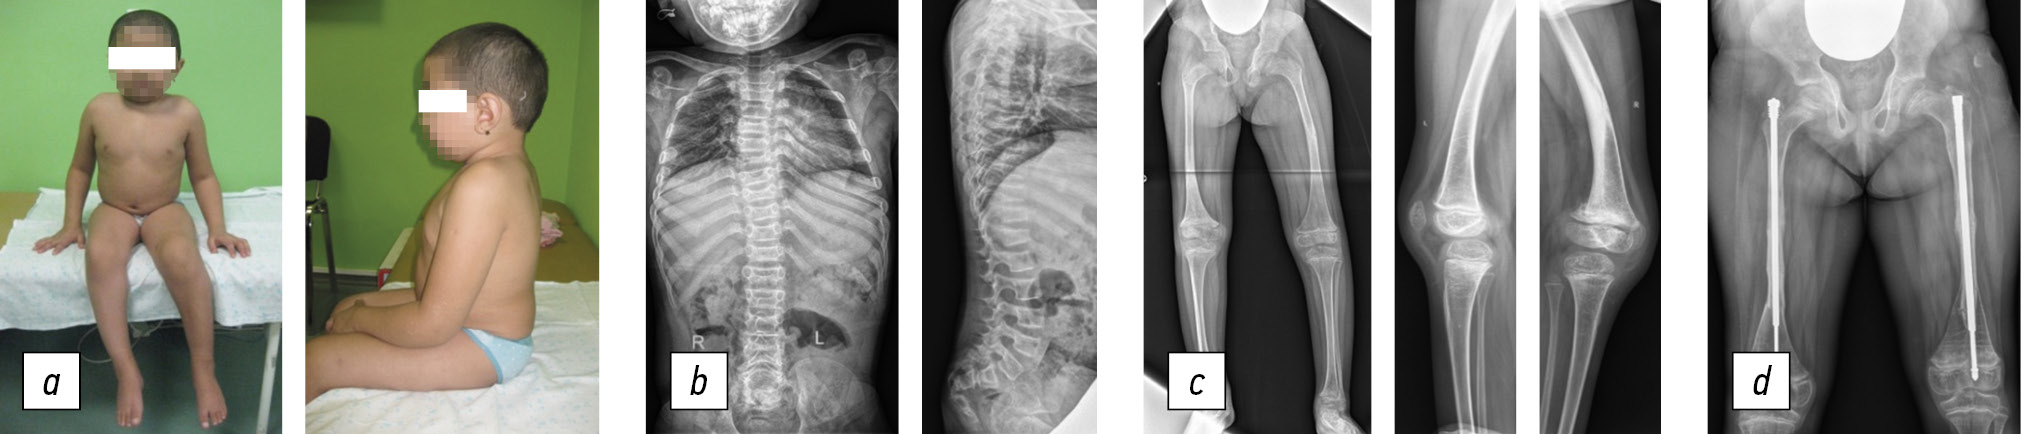

Clinical case 1

Patient H, delivered independently during the second term of her mother’s second pregnancy, had a birth weight of 3900 g and a height of 52 cm. No orthopedic pathology was detected. Since birth, patient H has been under the supervision of a neurologist because of birth trauma to the central nervous system. At age 1, patient H stopped standing and making attempts to walk. At age 3, the patient experienced a left femur fracture for the first time. Compression fractures of the ThXII–LI vertebrae were detected when she was 4 years old. She suffered three fractures of the right and left femur between the ages of six and eight. At age 6, examination showed a decrease in skeletal bone mineral density. Bisphosphonates were administered twice a year to treat osteoporosis, which helped reduce fractures. At age 8, corrective osteotomy of the right and left femur was performed for the first time, with fixation using a telescopic rod (Fig. 1). Standard consolidation periods followed osteotomy.

Fig. 1. Patient H, eight years old, Bruck syndrome, type 2: a, general view of the patient (does not walk); b, spine radiographs in anteroposterior and lateral projections: 10° frontal deviation of the spinal axis, wedge-shaped vertebrae; c, panoramic radiograph of the lower extremities in anteroposterior projection, varus-antecurvation deformity of the femurs; d, radiograph of the femurs in anteroposterior projection, intramedullary fixation with a telescopic rod